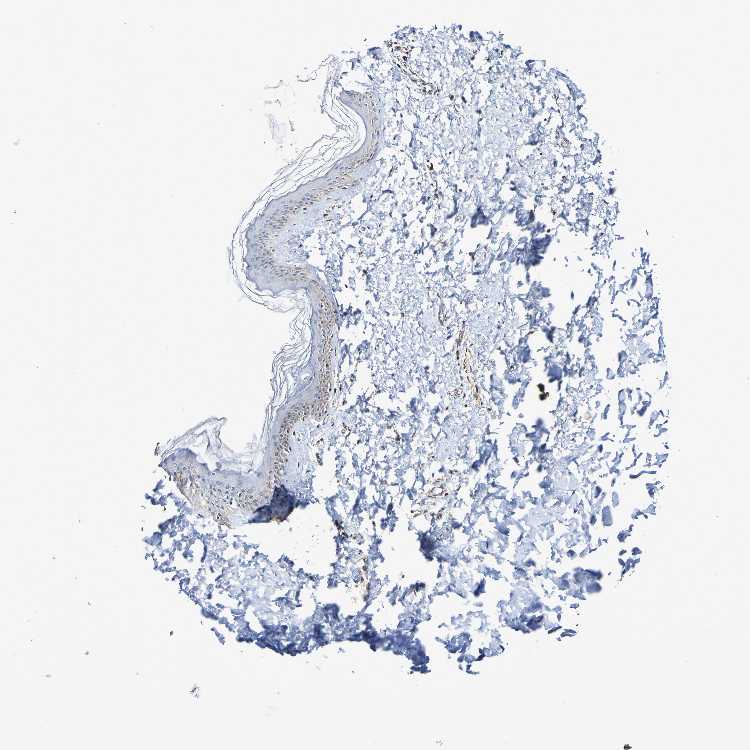

SKIN 1 - Antibody stainingi

Antibody staining in the annotated cell types in the current human tissue is reported as not detected, low, medium, or high, based on conventional immunohistochemistry profiling in selected tissues. This score is based on the combination of the staining intensity and fraction of stained cells.

Each image is clickable and will lead to virtual microscopy that enables deeper exploration of all samples and also displays staining intensity scores, fraction scores and subcellular localization as well as patient and tissue information for each sample.

Antibody HPA007615

Langerhans Medium

Fibroblasts Medium

Keratinocytes Medium

Melanocytes Not detected